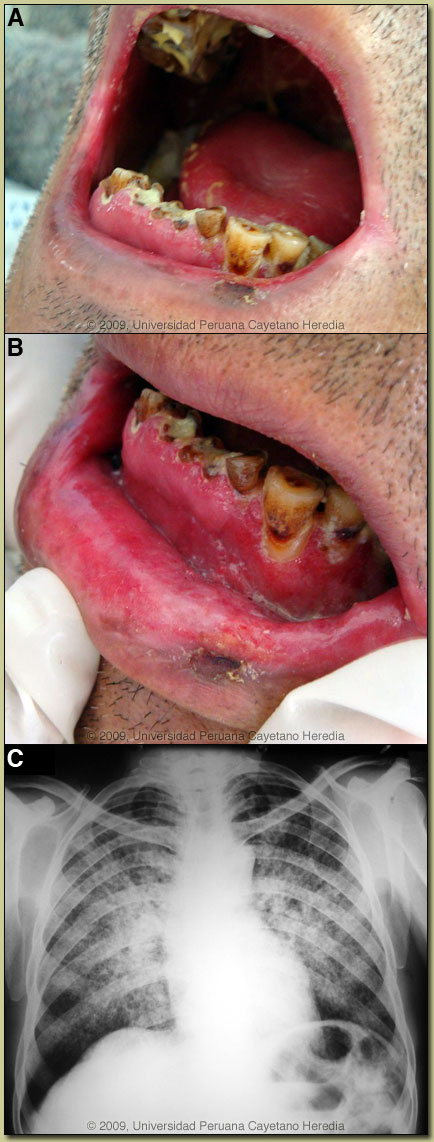

| Diagnosis: Paracoccidioides brasiliensis infection (chronic form) with mucosal involvement. |

The major differential diagnosis in Perú of oro-pharyngeal lesions in non-HIV infected patients would be mucosal leishmaniasis, paracoccidioidomycosis, carcinoma, or lymphoma. In Perú, leishmaniasis with destructive but painless lesions would be by far the most common. In general, oral lesions of paracoccidioidomycosis are painful, are frequently friable and bleed on contact, and gingival and buccal mucosa are frequently involved. The differential diagnosis for the lung disease includes: TB, histoplasmosis, lymphoma, cancer and cryptococcosis. This patient demonstrates the most typical radiographic pattern of paracoccidioidomycosis with bilateral mixed infiltrates (alveolar and interstitial), mainly located in the middle and lower lobes. Interstitial lesions may have a miliary, nodular or fibronodular patterns. Other patterns observed in these patients are hilar and mediastinal lymph node enlargement, cavities, and calcified lesions. Extrapulmonary disease is found in over 70% of cases and may involve skin, mucous membranes, lymph nodes, adrenals, abdominal organs and CNS (in 10%). Bacterial superinfection of ulcerative oral lesions when they occur is more common than with oral ulcers due to mucocutaneous leishmaniasis. This case is representative of the chronic form (adult type) of the disease, which is believed to represent reactivation of latent infection. This type represents approximately 94% of all cases in the experience at our institute (94 patients, up to 2001), and approximately 85% in the Brazilian series [Rev Soc Bras Med Trop. 2003;36(4):455-9]. In our experience the male:female ratio in chronic paracoccidioidomycosis is 20:1. TB coexists in up to 10% of patients with paracoccidioidomycosis. Cavitation and pleural effusion are less commonly seen than in TB. We have previously presented cases of two other clinical forms of paracoccidioidomycosis: (1) the juvenile form [Gorgas Case 2006-02]; and (2) the chronic progressive form [Gorgas Case 2003-07]. Paracoccidioidomycosis, also known as South American blastomycosis, is found in humid forested or lush green areas of the Americas from Southern Mexico south to Uruguay and Argentina. It appears to be most common in Brazil. The exact habitat of the organism is unclear but transmission is described as being entirely by airborne inhalation. However, we have observed cases with only oral lesions apparently associated with the use of tree leaves contaminated with fungal spores as toothpicks. Primary pulmonary infection may be asymptomatic and self-limited, but even with treatment, will produce at least moderate pulmonary fibrosis. Rural adult male agricultural workers between 30-60 years of age are most affected by the infection. Travelers spending less than 6 months in an endemic area are unlikely to acquire paracoccidioidomycosis. Sulfonamides, ketoconazole, itraconazole, and amphotericin B are all effective therapies. Amphotericin should be reserved for severe cases such as this one where there is some respiratory compromise. For typical cases, itraconazole 100-200 mg/day for 6-9 months is regarded as the treatment of choice when it is available and affordable. Relapses are common with less than 6 months therapy and expert opinion is now that 1 year is not necessary. In the developing-world setting, ketoconazole is likely equally effective and is usually less than half the cost. However, 12 months of therapy with ketoconazole is generally recommended. In severe cases with a high yeast burden, such as in our case, the practice is to induce such patients with amphotericin B for at least 10 days at 1 mg/kg, then switch to oral itraconazole 200 mg per day, to complete a total duration of at least 9 months. |